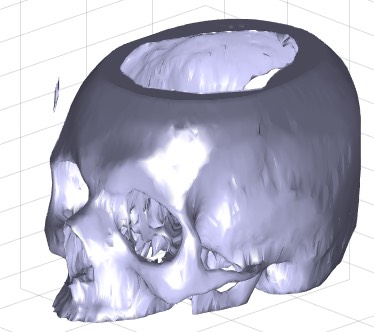

exp_2017_02_21- EXPERIMENT SCRIPT to load and precalcuate a skull bone surface model |

| % exp_2017_02_21 - EXPERIMENT SCRIPT to load and precalcuate a skull bone surface model % (by Tim Lueth, VLFL-Lib, 2017-FEB-21 as class: EXPERIMENTS) % % exp_2017_02_21 % |

SGofVMdelaunay(V,vs,s)- returns a surface model for a delaunay reconstructed volume model |

| % SGofVMdelaunay(V,vs,s) - returns a surface model for a delaunay reconstructed volume model % (by Tim Lueth, VLFL-Lib, 2017-FEB-17 as class: VOXELS) % % This fnctn takes about 20 second for a 256 x 256 x 100 voxel model. % (Status of: 2017-02-18) % % See also: VLFLofVMdelaunay, VLFLofVMmarchcube, TR3ofVM, SGofVMmarchcube % % [SG,TR4]=SGofVMdelaunay(V,[vs,s]) % === INPUT PARAMETERS === % V: Voxel Model (~=0 is reconstruction) % vs: voxel size, optional % s: step size % === OUTPUT RESULTS ====== % SG: Solid Geoemtry % TR4: Delaunay tetrahedron model % % EXAMPLE: % [V,vs]=VMreaddicomdir('AIM_DICOMFILES'); % [a,as]=VMresize(V,[0.5 0.5 0.5],vs); % SG=SGofVMdelaunay(a>1400,as); % SGcut(SG,40); % c=CPLofSGslice3(SG,20); % PLFLofCPLdelaunay(c); % PLFLofCPLpoly(c) % |

SGofVMmarchcube(V,vs,cl)- returns a surface model by the marching cubes |

| % SGofVMmarchcube(V,vs,cl) - returns a surface model by the marching cubes % (by Tim Lueth, VLFL-Lib, 2017-FEB-17 as class: VOXELS) % % This fnctn uses the MarchingCubes fnctn from Matlab Central written by % Peter Hammer in 2011 based on the Octave fnctn written by Martin Helm % (www.mhelm.de/octave/m/marching_cube.m) in 2009. It contains also code % from Oliver Woodford for removing duplicated vertices. (Status of: % 2017-02-23) % % See also: VLFLofVMdelaunay, VLFLofVMmarchcube, TR3ofVM, SGofVMdelaunay % % SG=SGofVMmarchcube(V,[vs,cl]) % === INPUT PARAMETERS === % V: Logical Volume Model % vs: voxel size, optional % cl: closes open facets by adding empty planes; default is true % === OUTPUT RESULTS ====== % SG: Vertex list % % EXAMPLE: [V,vs]=VMreaddicomdir('AIM_DICOMFILES'); % [a,as]=VMresize(V,[0.5 0.5 0.5],vs); % SG=SGofVMmarchcube(a>1400,as); % SGcut(SG,40); % c=CPLofSGslice3(SG,20); % PLFLofCPLdelaunay(c); % PLFLofCPLpoly(c) % |